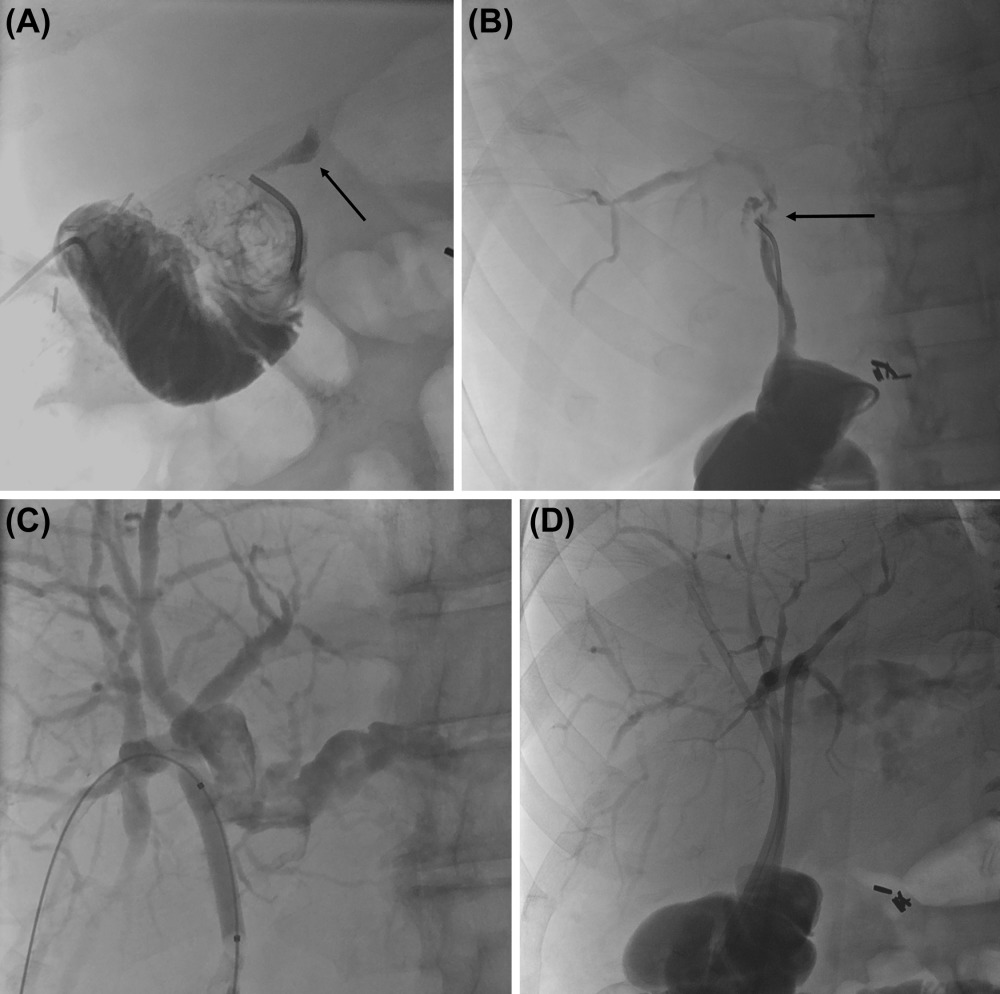

The authors discuss how IR can help manage hepatic artery thrombosis and hepatic artery stenosis.